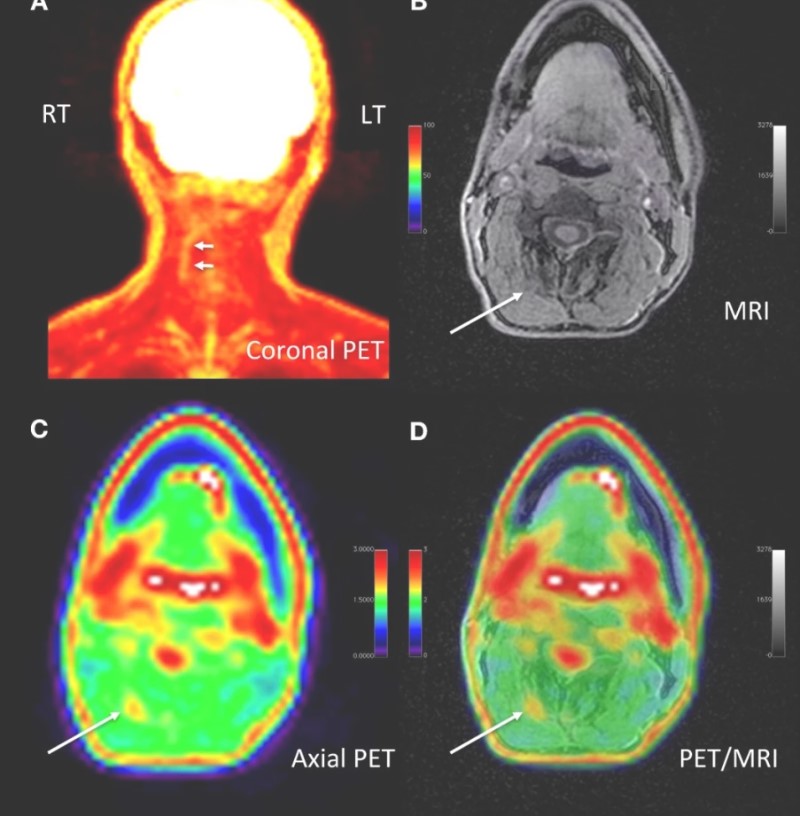

İşte araştırmamızda PET/MRI’ın kişinin ağrılarına giden tam moleküler nokta atışı yapabilme potansiyeli olduğunu araştırdık,” diyor projede yer alan araştırmacılardan Sandip Biswal. Kronik ağrısı olan 65 kişi üzerinde yapılan çalışmada tüm vücut PET/MRI taraması yapıldı ve 18F-FDG izleyicisi ile dokuda glukozun yükseldiği noktalar belirlendi. Bu eşsiz teknoloji sayesinde 58 sübjede ağrı konumları tam olarak konumlandırıldı. Yeni klinik bilgi sayesinde, bu sübjelerin 40’ında ağrı yönetim tedavi planları değiştirildi. Örneğin, araştırmacılar  yıllardır kronik boyu ağrısı çeken ve tedavilere yanıt vermeyen bir hastanın taramayla FDG yükselmesine bağlı olarak, spesifik ağrı konumu belirlendi. Ağrı kaynağının, bir siniri sıkıştıran kılcal damarlar olduğu belirlendi.

Beyaz oklar kronik boyun ağrısının kaynağını gösteriyor Bu görüntülemeden yola çıkan cerrah, lysis adı verilen bir operasyonla kişinin yıllardır çektiği acıyı büyük oranda hafifletti.